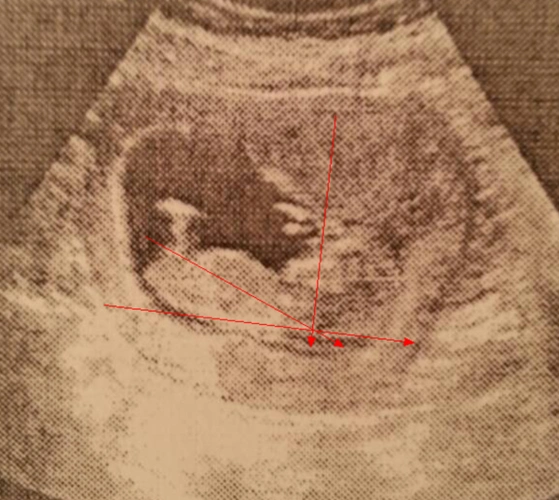

孕12周nt检查

怀孕12周男女区别图怀男孩女孩nt单子揭秘2

12周nt单子尾椎亮点图孩子裆部有凸起的亮点是男孩